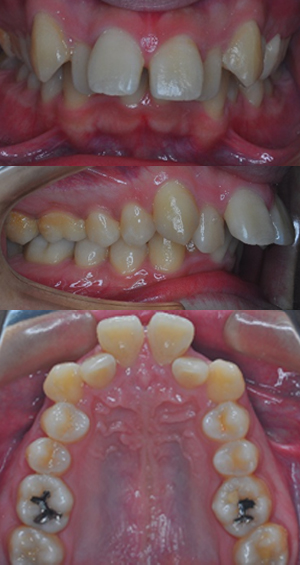

| 主訴 | 反対咬合が気になる |

|---|---|

| 診断 | 下顎前突 |

| 治療内容 | 非抜歯・非外科 マルチブラケット法 |

| 治療期間 | 3年間 |

| 治療金額 |

|

| 開始年齢 | 15歳8か月 |

| リスク副作用 | 矯正中は、ブラッシングが不十分だと、虫歯や歯肉炎になるリスクがあります。 また、治療中は治療に対する患者さん自身の協力が必須です。特に反対咬合は、顎の成長変化が治療に影響を及ぼす場合が多く、安定するまで治療期間や治療後の管理が長期にわたることがあります。 治療後の保定管理を怠ると、後戻りが起こりやすくなるため、その後の管理も必要です。 |